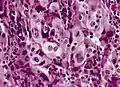

Anaplastic tumor cells. Large cell carcinoma.

Large cell carcinoma.